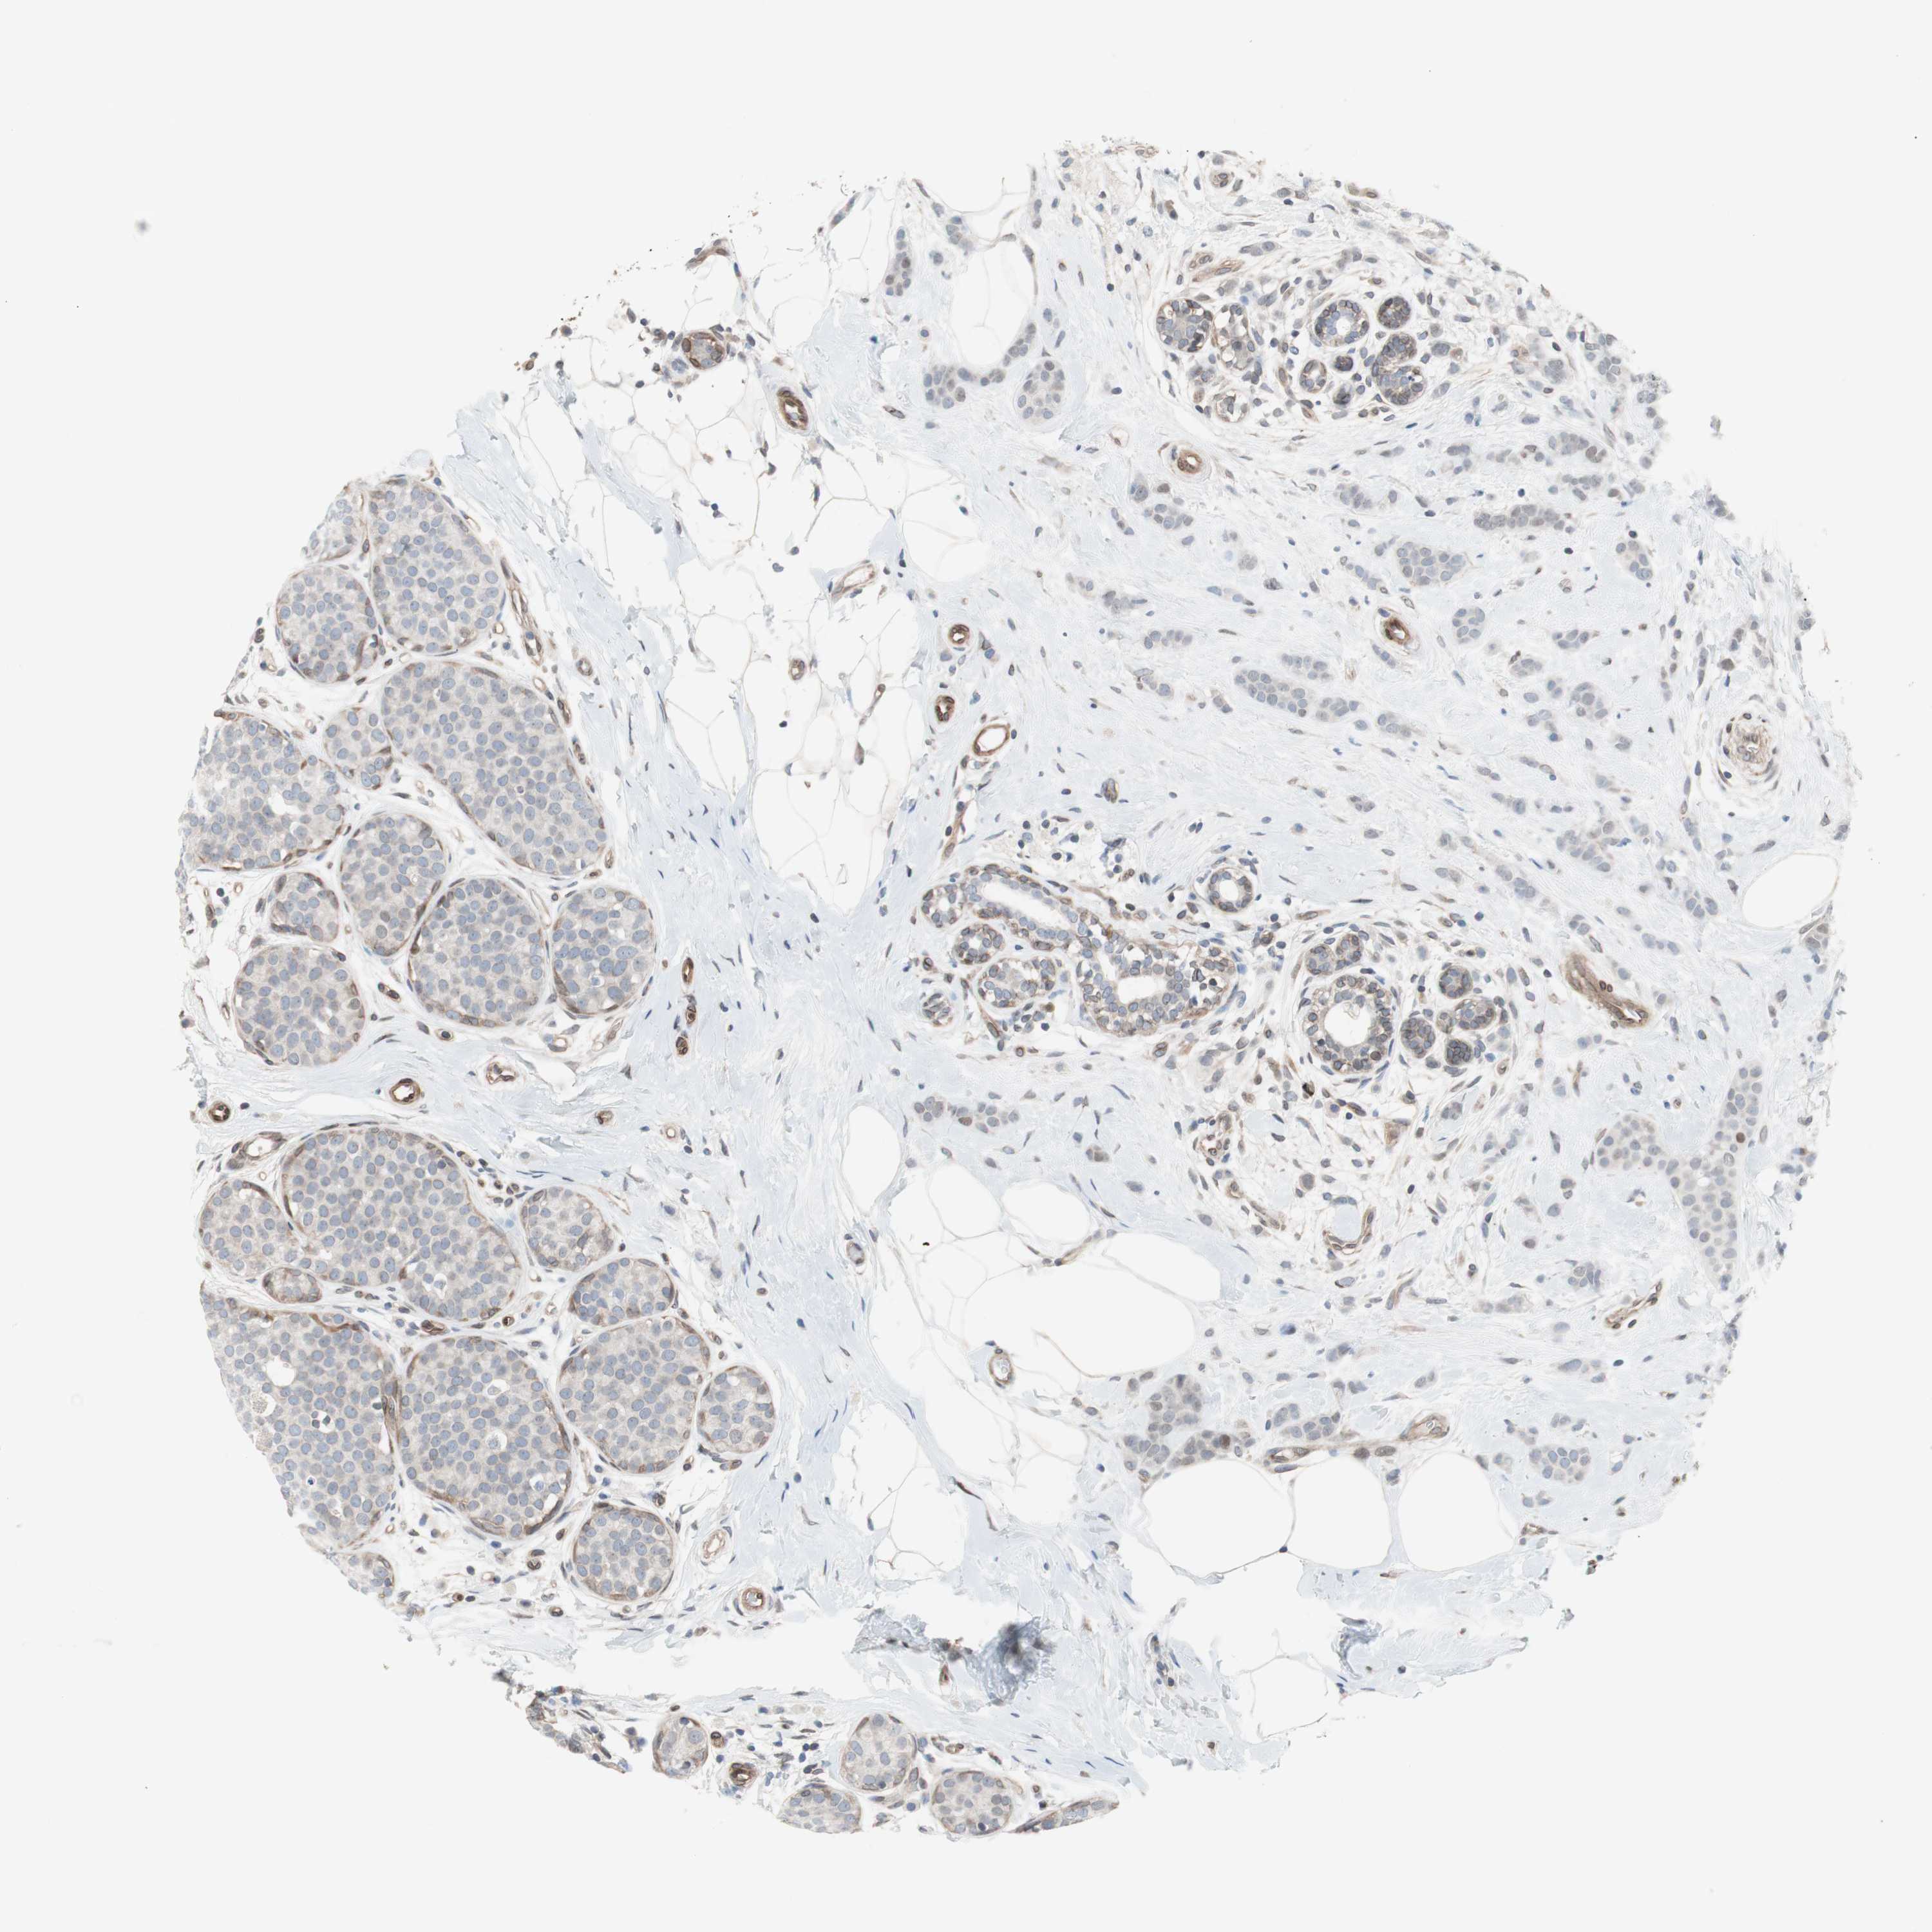

CANCER BREAST CANCER Show tissue menu

BRCA TCGA BRCA VALIDATION PROTEIN EXPRESSION

Breast cancer

Human cancer